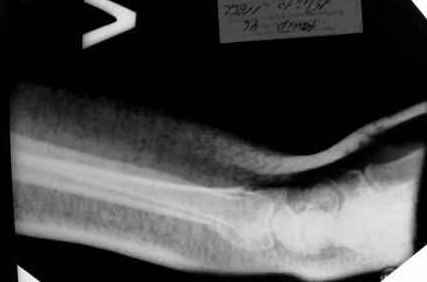

15.12- перелом луча в Москве. Там же репозиция, гипс. Дальнейшее лечение у нас в ЦРБ.

20.12.- вторичное смещение в гипсе 21.12- под внутривенным наркозом- репозиция, гипсовая лонгета.

1.Прошу объективно оценить качество нашей репозиции на момент 21.12. (неужели так плохо?). Что на снимках при снятии гипса- сам вижу.